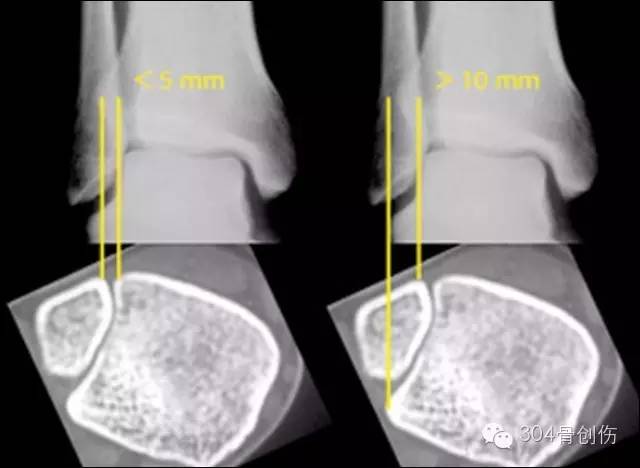

CT 与 MRI 检查意义

Nielson等以传统X线测量与MRI进行对比临床实验研究,来评价标准X线测量在踝部骨折时预测下胫腓联合损伤的可靠性,结论认为X线测量不能预测踝部骨折时是否存在下胫腓联合损伤,X线上正常下胫腓关系不能排除下胫腓联合损伤。

Takao等临床研究报导,以关节镜作为对照标准,X线正位片和MRI诊断下胫腓联合损伤的敏感性、特异性和准确性分别为:44.1%与100%、63.5%和100%、93.1%与96.2% (Takao研究引用的X线诊断标准为下胫腓间隙大于5mm、下胫腓重叠小于10mm为异常)。认为X线片有助于评价踝部骨折和韧带损伤的情况,但准确性不够满意。与更为准确的CT, MRI以及踝关节镜相比,传统的X线诊断价值己越来越受到怀疑,己不能作为诊断下胫腓联合损伤的唯一依据。

Ebraheim等证实CT扫描对下胫腓联合损伤诊断比X线平片更容易可靠,敏感性更高。Ebraheifn等对尸体标本进行CT扫描发现,大部分2mm的下胫腓分离可以通过CT扫描发现并确诊,但无法识别1mm以内分离。而X平片仅能发现3mm以上的分离。CT扫描可以克服X线片上重叠影和投照体位的干扰,轴向扫描图像上胫腓间隙内部被清晰地显示,测量相关数值与健侧对比能准确的判断是否存在下胫腓分离。

CT 诊断

2013年加拿大Nault等研究,判定腓骨有无旋转、侧方和前后移位,相对简单,可信度较高。